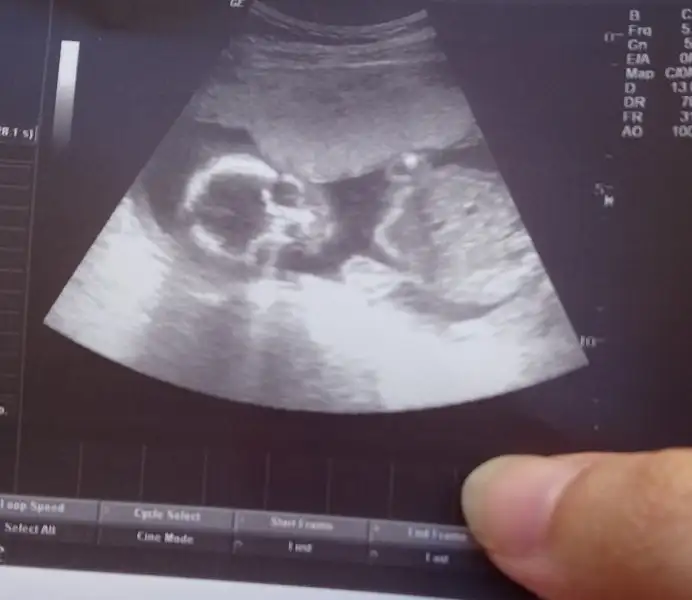

Valla hiçbirşey anlamadım toplasan 5 dk bakmadilar sinir oldum çıktım güya özel hastaneye gittim tip a gitseydim diye pişman oldum sadece bacak karin ölçümlerine baktı eli yüzü düzgün kalbi güzel atiyo dedi cinsiyet kesin kız dedi zaten simsiyah ekrandi göremedim hiçbirşey.tekrar kadin dogumcuya gidip ben yüzünün fotosunu istiyorum hicbisi göremedim dedim oda bu fotoyu verdilerGüzel haberlerini ve anlatmanı bekliyorum canım. Dr neye baktı, nelere önem verdi ve s. Benimki 3 gün geriden geliyor hep.